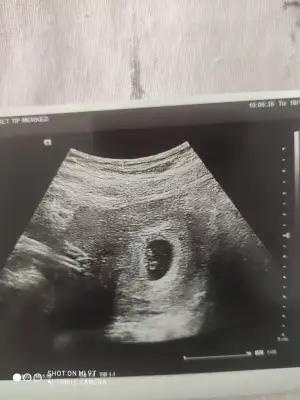

Başka USG paylaşın12 haftalık USG bu çok teşekkür ederim![]()

8 haftalık budaBaşka USG paylaşın![]()

Karından ise erkek vajinalsa kiz tabiki en iyi 11 12 13 haftalar8 haftalık buda